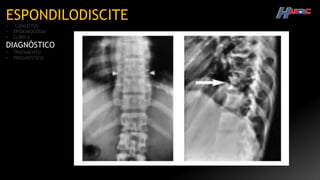

ESPONDILODISCITE

TC

Destruição do

corpo vertebral